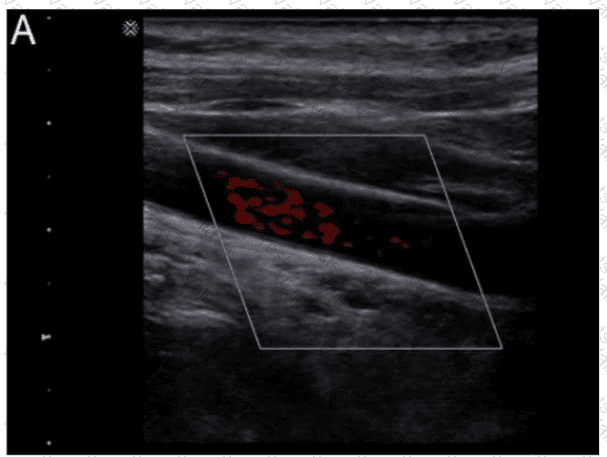

What adjustment is needed to optimize the color in the image below?

Question # 3

Options:

A.

Decrease gain

B.

Increase wall filter

C.

Decrease persistence

D.

Increase pulse repetition frequency